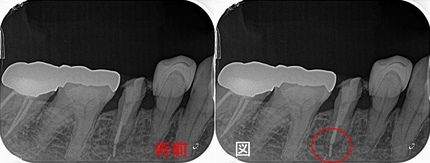

患者さんは20代女性

矯正中に来院して頂いた際には小さな虫歯だったのですが、

矯正が終わった頃には歯肉縁下まで入る大きな虫歯になってしまっていました。

それに伴い骨も大きく無くなっています。

今回のケースは、矯正治療で第2大臼歯も近心傾斜させてしまっており、上にレジンで立ち上げるスペースも無い為ヘミセクション(分割抜歯)を選択しました。

分割確認のレントゲン

ヘミセクション後 フルジルコニアクラウンを入れさせてもらったのですが・・・

クラウンを入れて2年半後にコアごとクラウン脱離

骨の所見を見ると、咬む力による問題+クラウンに強すぎる材料を使ってしまったここと推測

患者さんに謝り、もう一度根管治療からやり直させてもらいました。

ヘミセクションの際に自分がレジンコア作るべきだったと反省。。。